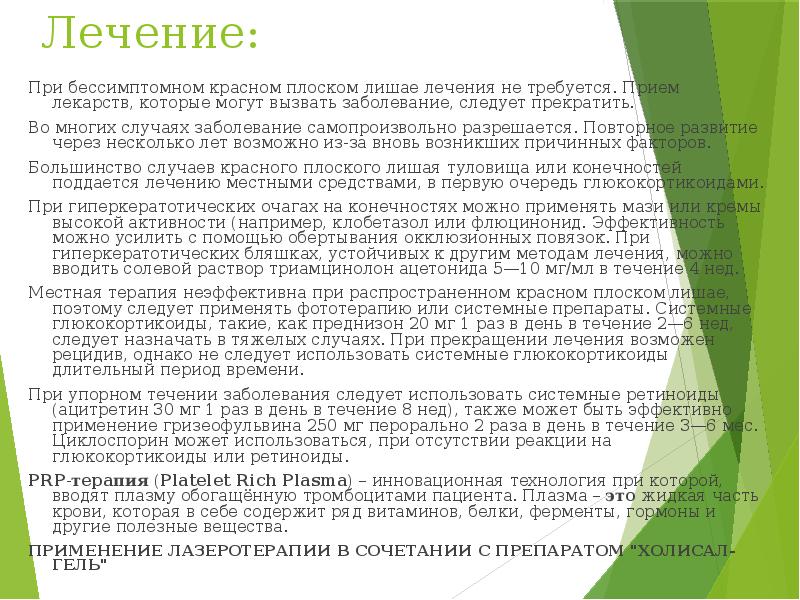

Фото Красного Плоского

Фото Красного Плоского 103 фото